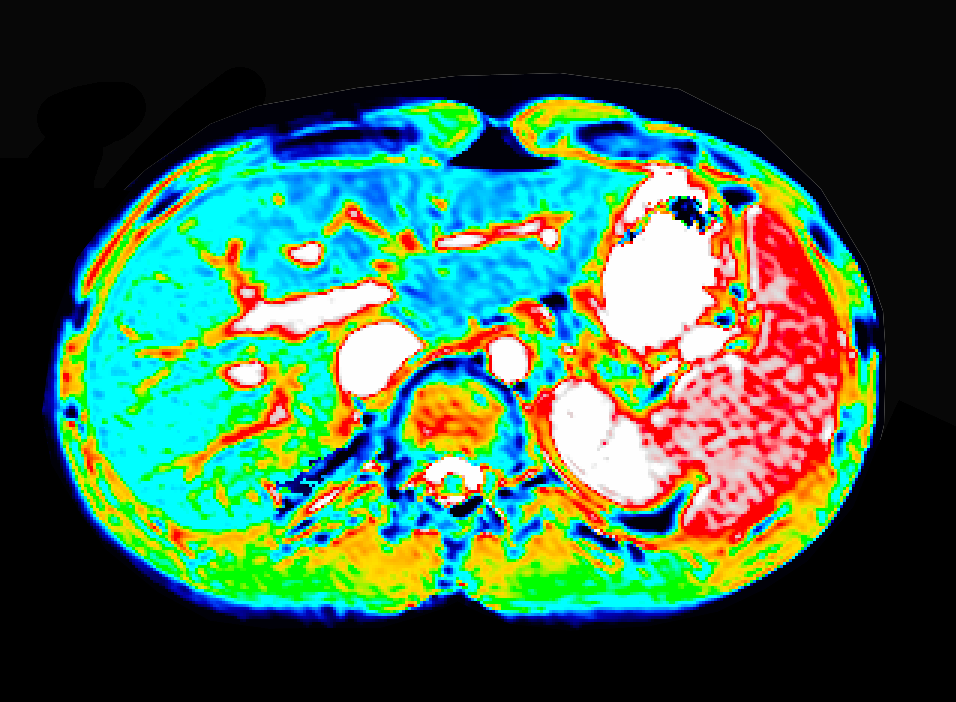

Inflammation

Inflammation biomarkers for arthritis, autoimmune disease, and organ injury.

- DCE-MRI Ktrans biomarkers of microvascular function

- Joint imaging in rheumatoid arthritis and osteoarthritis

- Renal imaging biomarkers including ASL, T1, T2, ADC

- Hypoxia and pH imaging methods (BOLD, OE-MRI, CEST)

- Sensitive, repeatable measurements with small cohorts